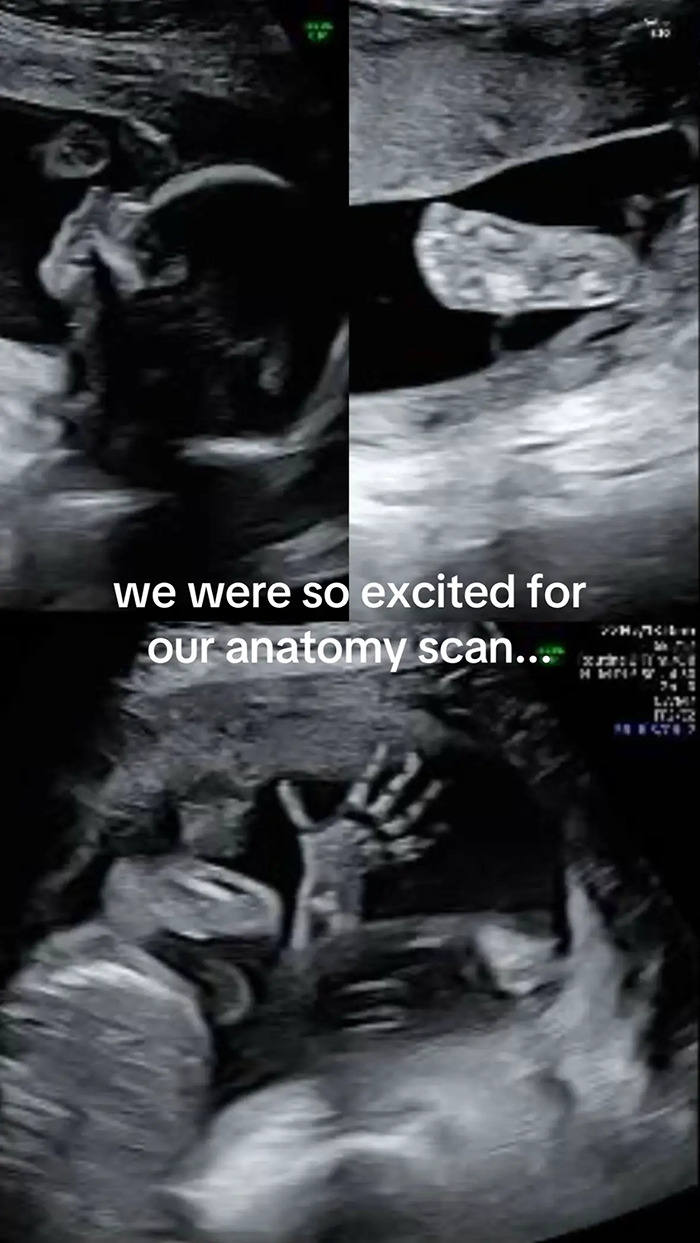

Inês Egner, an influencer and soon-to-be mother from Portugal, couldn’t believe her eyes when her 20-week anatomy scan revealed something unexpected, and hilarious.

Instead of her baby, the machine showed what appeared to be the face of her dog, Goulash, staring back at her.

“We were so excited for our anatomy scan,” Egner wrote across the first slide of her post. “Only to get our photos back and realise our son looks remarkably like our dog!”

Speaking to her followers and media outlets, Egner recounted how she first noticed the likeness while looking through the photos with her best friend and husband after the scan.

“We were skimming through them together, the three of us, as you do, admiring the little hands, the little nose… until we came across that picture and my friend goes, ‘Wait, doesn’t the baby look just like Goulash?’” she told People Magazine.

“Hard to unsee the uncanny similarity after that,” she added. “My husband and I instantly started laughing because we could see it too.”

As for what created the strange, dog-like image. Egner explained to her viewers that it was most likely the result of a weird angle.

“They were checking from the angle of his chin, checking up his nostrils and his eyes,” she said.